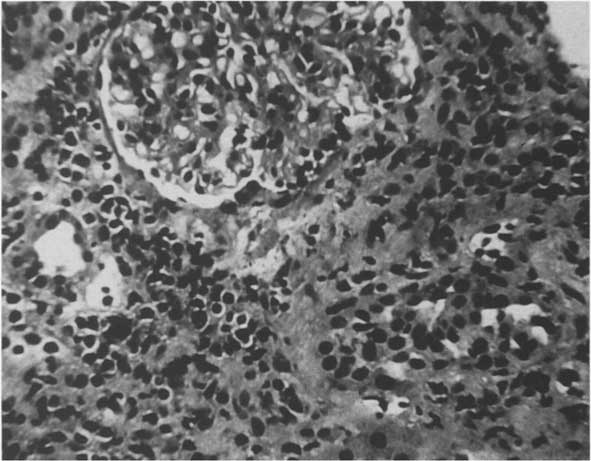

Abdominal ultrasound examination showed a prominent gall bladder and two large echogenic kidneys measuring 10.6 cm. There was no evidence of obstruction. A percutaneous renal biopsy was performed.

In our patient, acute interstitial nephritis occurred in the setting of KD. Our patient displayed anemia, acute renal insufficiency, oliguria, and tubular dysfunction. Urinalysis was significant for pyuria but not proteinuria, hematuria, or glucosuria.